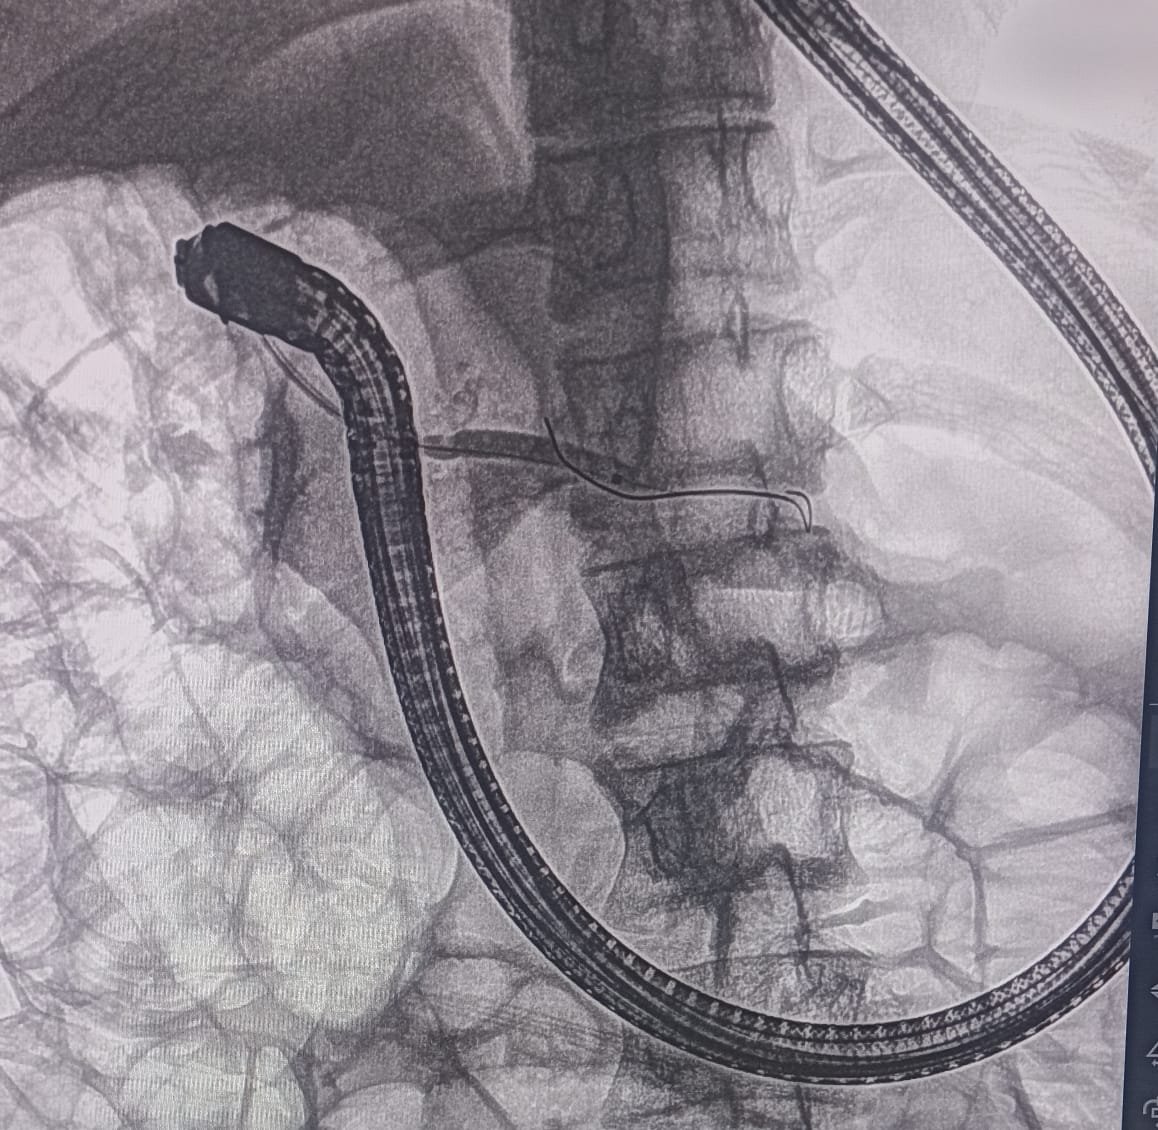

Chronic Pancreatitis ERCP Image 4

Stent Placement

Communication of duct of Santorini was found to be of very small caliber. Cannula was passed into the pancreatic duct of body and tail. Duct of Santorini was dilated up to 4mm with biliary hurricane balloon. A 7Fr x 7cm single pigtail pancreatic stent was placed in the PD.

• 7Fr x 7cm single pigtail pancreatic stent placed